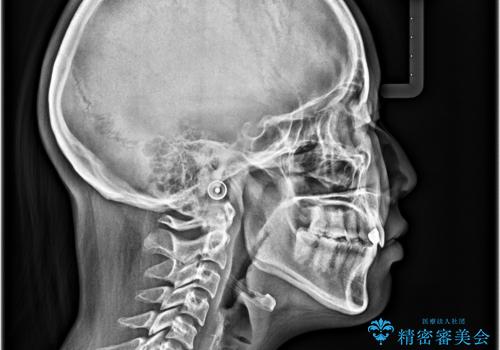

飛び出した前歯 インビザラインを用いた抜歯矯正治療

治療途中で地元へ転居され、飛行機での通院となったため、治療期間が長くなりましたが、自然で整った口元に仕上げることができました。

上下前歯同士の距離が離れているため、上顎左右第一小臼歯2本を抜歯することで前突を改善することとしました。

しかしながら、左右ともに側切歯が矮小歯であるため、矯正治療で矮小歯前後にスペースを作り、矯正治療後にオールセラミッククラウンにて補綴治療を行うこととしました。